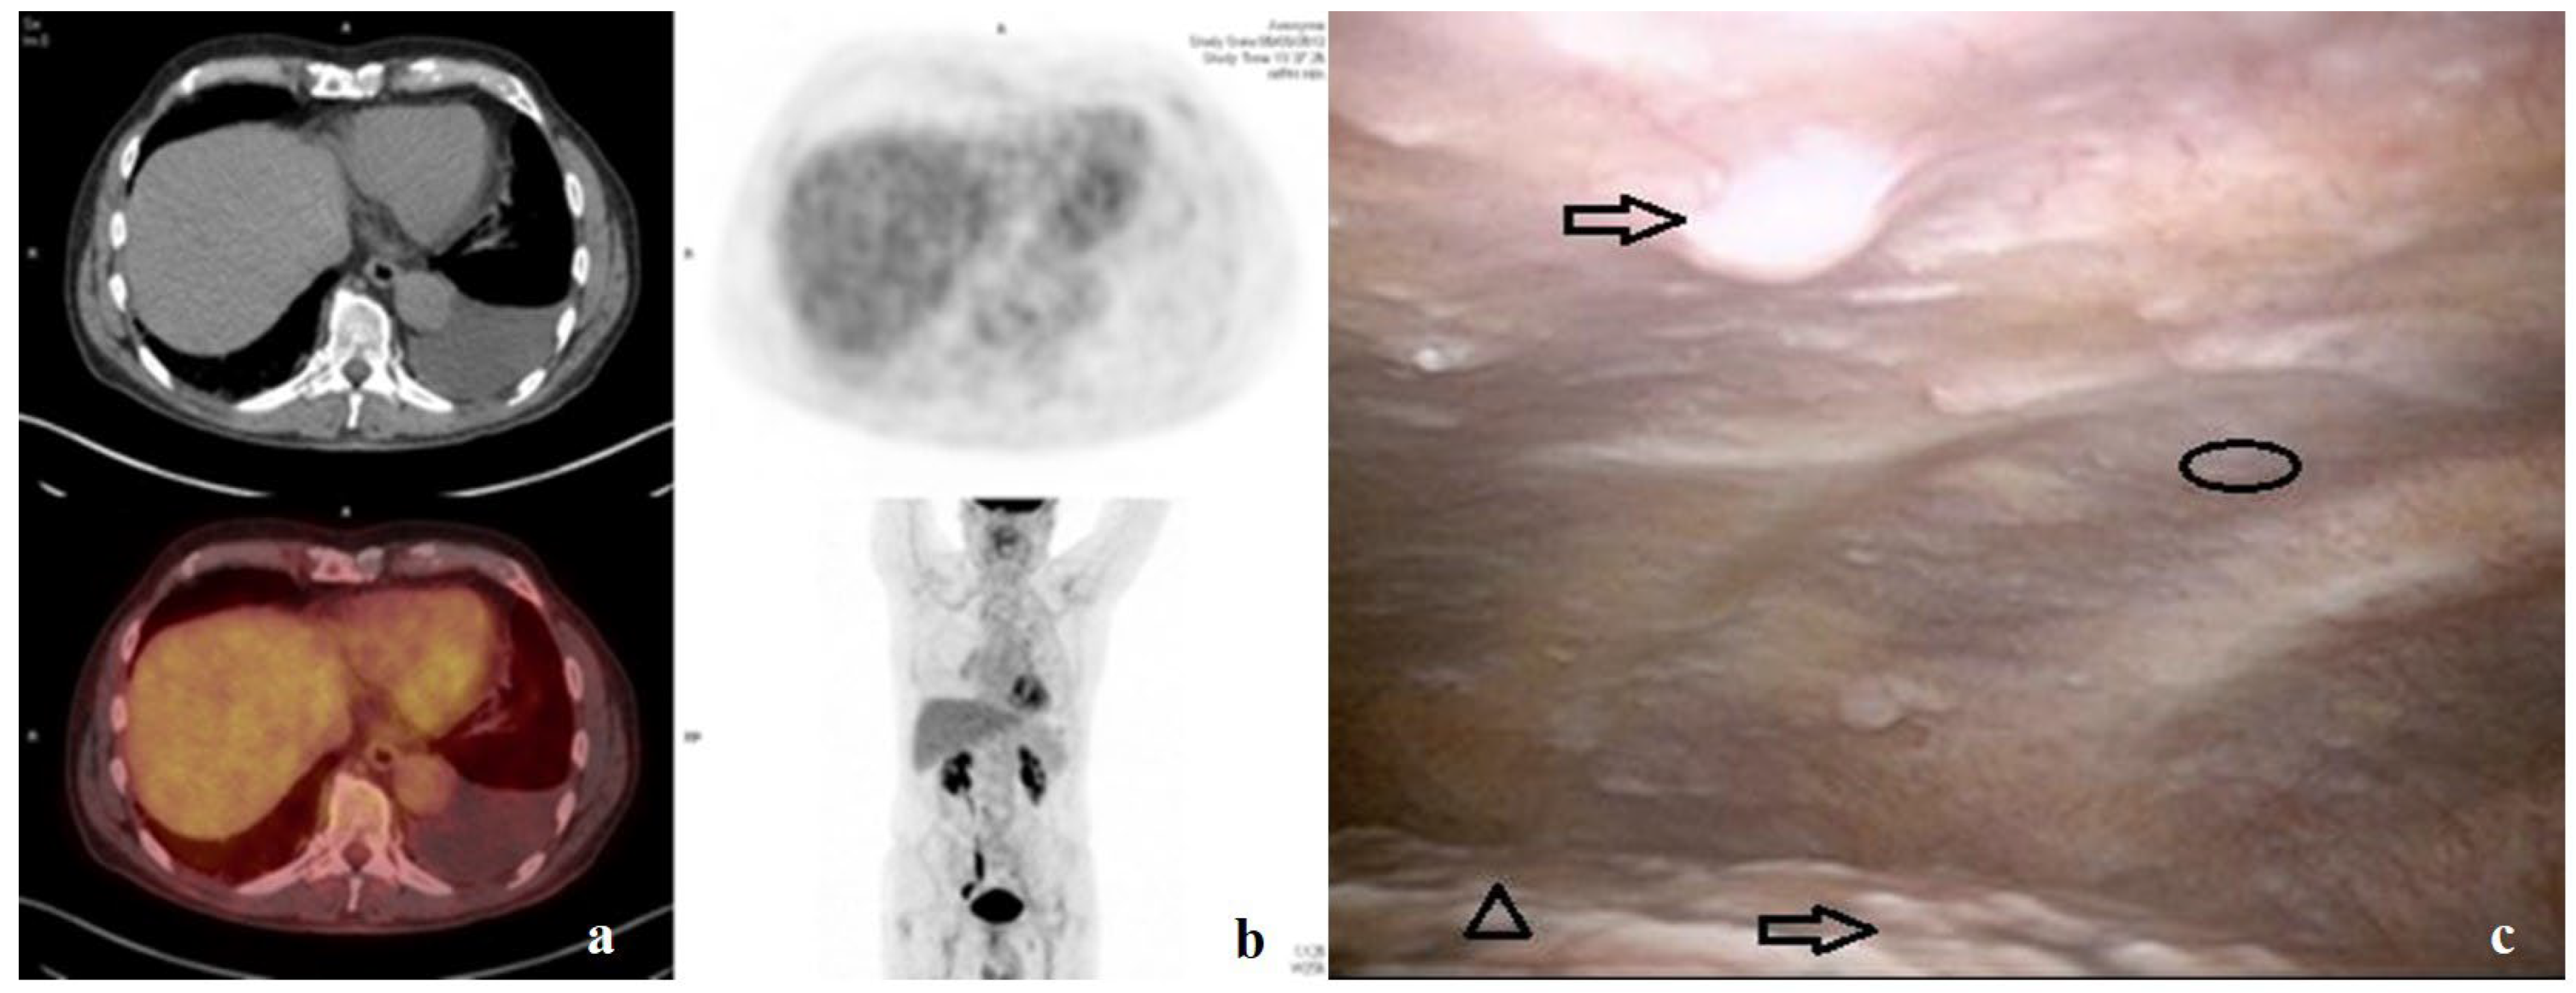

7. Clinical Case and Practical Technique